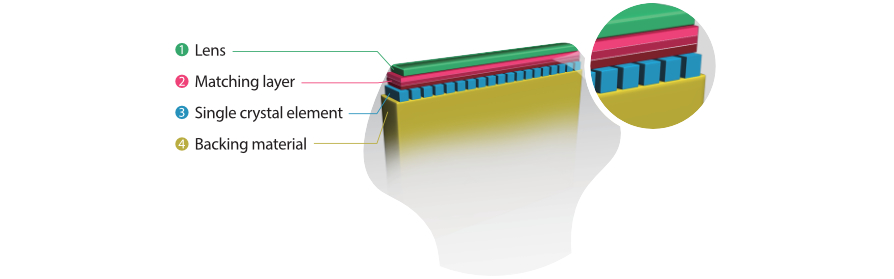

3T-Einkristall-Schallkopftechnologie

F├╝r sch?rfere Bilder sind alle mit dem M9 kompatiblen Sonden mit Mindrays einzigartiger 3T-Schallkopftechnologie ausgestattet. Das durch die Einkristalltechnologie verbesserte M9 bietet bessere Penetration und dynamischen Farbfluss, insbesondere bei der Untersuchung schwieriger Patientinnen oder Patienten.